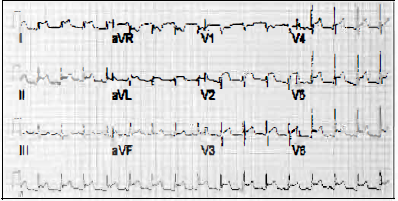

Paciente gestante de 32 anos de idade, com passado de palpitação por taquiarritmia, apresenta o ECG abaixo:

O diagnóstico do ECG é: